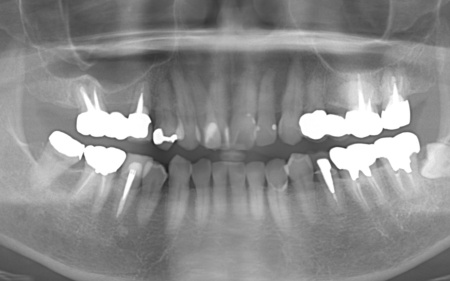

60代女性 歯根が割れて痛む歯を抜いてインプラント治療で噛み合わせを回復した症例

| カウンセリング・診断結果 | 拝見したところ、右上の歯には、欠損部位前後の歯を土台として橋を渡すように連結した被せ物「ブリッジ」が装着されていました。 しかし、土台となっている手前の歯(第2小臼歯)は歯根が割れており、同じく土台となっている奥の歯(第2大臼歯)は歯根の先に膿の袋ができる「根尖病巣(こんせんびょうそう)」が認められます。 さらに、ブリッジ部位の歯茎は腫れ、痛みもあるとのことでした。 かかりつけの歯科医院では、細菌感染を抑える薬を飲んだり、歯を少し削って噛み合わせを調整したりして様子を見ていましたが、口腔内の状態が改善せず、次は抜歯をする必要があると説明を受けたそうです。 また抜歯後に歯を補う方法のひとつにインプラント治療がありますが、患者様の場合は治療に必要な骨量が確保できないため難しいとされ、取り外し式の入れ歯になるとのことでした。 患者様はかかりつけ医からの説明が十分でないと感じていたため、当院にセカンドオピニオンで来院されています。 以上のことから、まずはブリッジ周辺の治療を行ったのち、欠損部を補う治療方法をしっかりと検討する必要があると診断しました。 |

| 行ったご提案 ・治療内容 | 痛みが出ているブリッジ周辺の治療として、ブリッジの土台となっていて、歯根が割れている手前の歯(第2小臼歯)は抜き、根尖病巣を発症している奥の歯(第2大臼歯)は、根管治療を行います。 根管治療とは、感染した神経を取り除いて、歯根内部を清掃・消毒する治療方法のことです。 抜歯と根管治療を行ったあとは、欠損部を補うために、2本のインプラントを埋入する方法を提案しました。 インプラントを埋入するために必要な骨量が足りない場合は、鼻の空洞(上顎洞)の粘膜を少しずつ押し上げて骨を増やす「ソケットリフト」を併用することもお伝えしています。 インプラント治療のメリット インプラント治療のデメリット それぞれの方法について丁寧にお伝えした結果、治療に同意いただきました。 まずは、右上手前の歯(第2小臼歯)を抜きました。 抜歯後は、インプラント治療を行うために、歯を支える骨(歯槽骨)の回復を待つ必要があり、最低でも6ヶ月を要します。 約2ヶ月後、インプラントと骨が結合したことを確認して、右上奥歯2本の仮歯を作製し、手前の歯槽骨が再生するまで経過観察を継続します。 約4ヶ月後、歯槽骨の再生が確認できたため、もう1本のインプラントを埋入しました。 当院のインプラント治療は、施術の安全性と長期的な使用を可能にすることを優先して治療を行うため、通常は抜歯後に歯槽骨の治癒を待ってからインプラントの埋入を行っています。 右上奥歯2本に仮歯が入り、噛み合わせが安定した状態になったため、根尖病巣を発症している右上奥歯の治療を開始します。 また、インプラントに装着する人工歯を作製する前に、歯科医院で歯を白くするオフィスホワイトニング治療を希望されたため、治療期間がやや長くなっています。 最後に、完成した人工歯を装着し、見た目や噛み合わせに問題がないことを確認して、治療を終了しています。 |

治療前

治療中

治療後